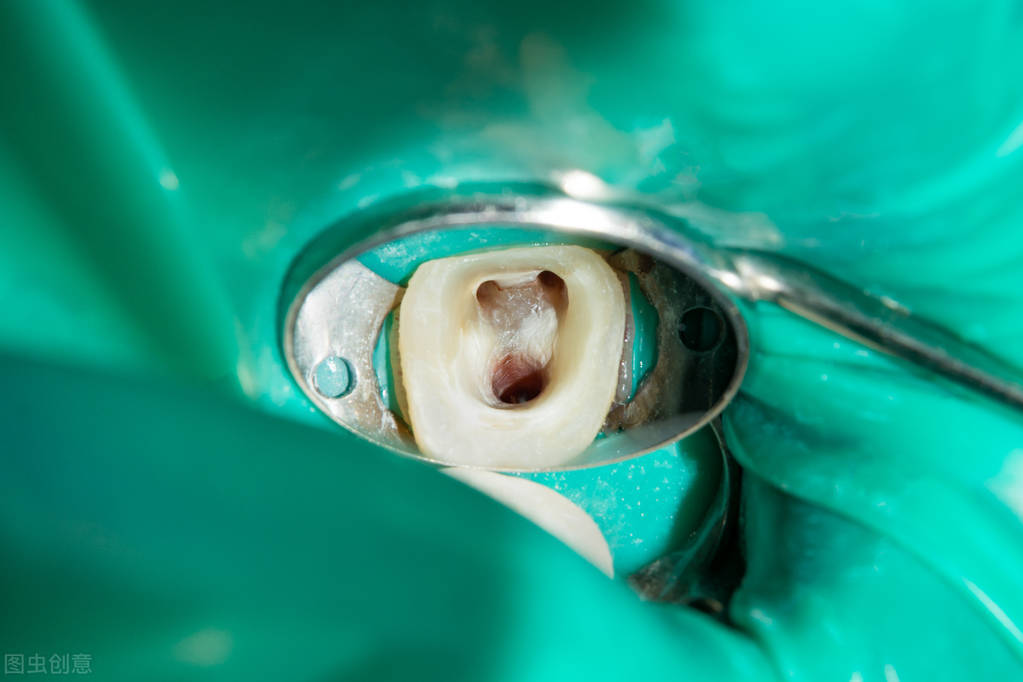

简单来说: 根管治疗,就是通过根管锉等医疗器械,清除牙齿内部被病菌感染的组织(牙髓和牙神经等),从而达到牙齿治疗的目的。

根管锉深入根管

根管治疗可以简单理解为三步:

① 根管预备: 使用根管锉等医疗器械,清除牙体内的病损组织。

② 根管填充: 使用牙胶、根充糊剂等材料,填充根管,消除死腔,防止再感染。

③ 佩戴牙冠: 部分人群需制作并佩戴牙冠,防止牙齿破裂。